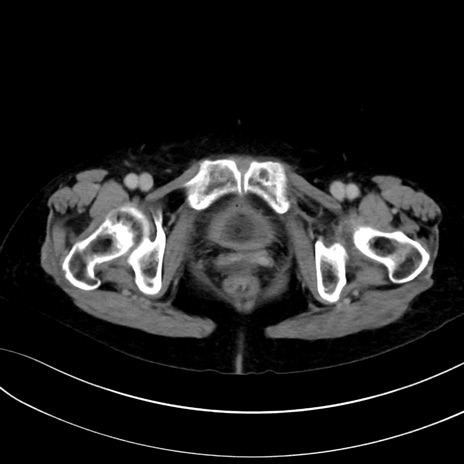

症例13 CT(横断像)1日半後